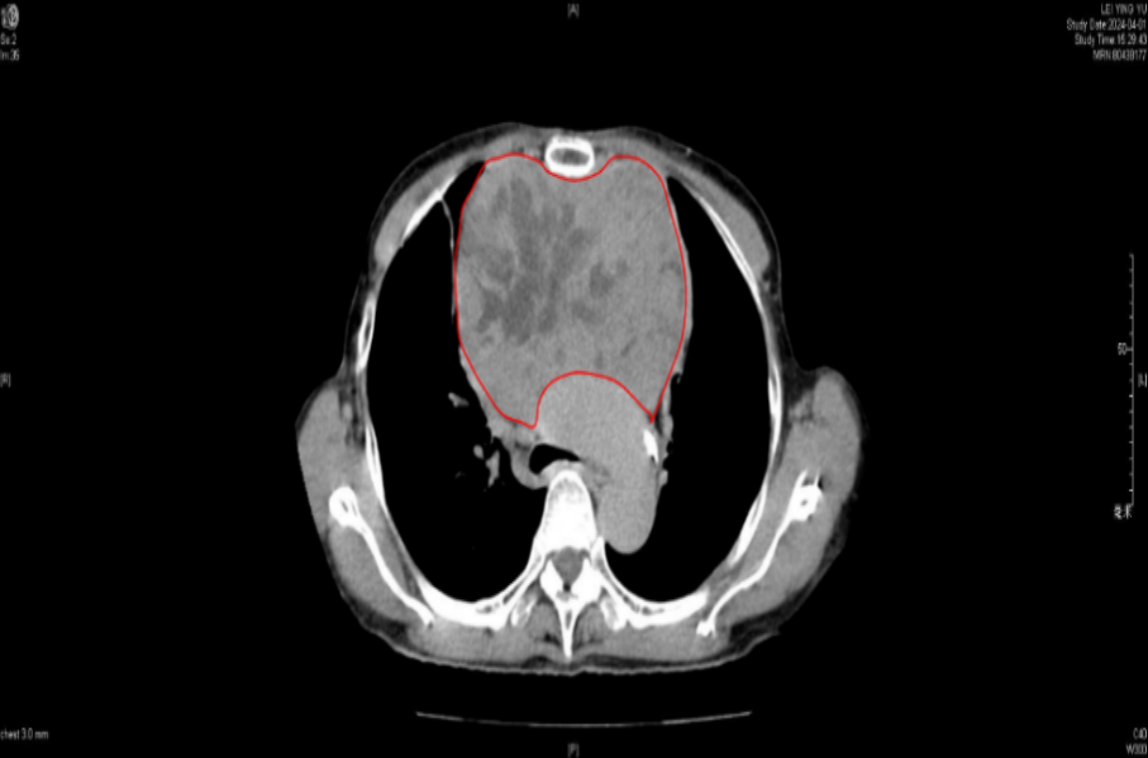

被咳嗽、胸闷折磨多日不见好转,家人带着雷婆婆来到医院检查——胸腔里竟然长了个超过14厘米的巨大肿块!这个硕大无比的肿物就像一个“巨石”顶住雷婆婆的胸口,还压迫了心脏和气管!

红色画圈部分为肿块